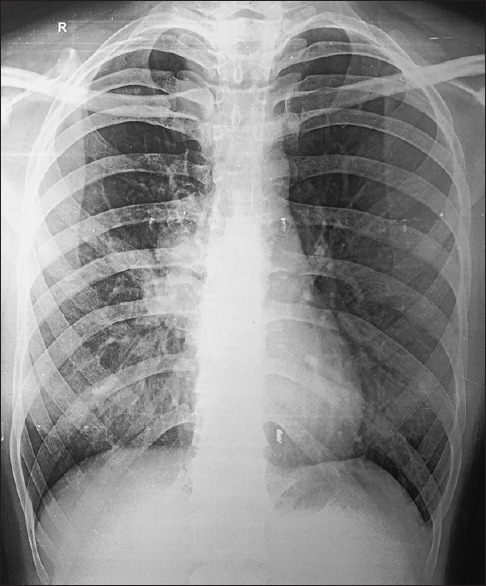

Abstract: In patients with severe asthma with allergic bronchopulmonary aspergillosis (ABPA), a variety of radiological manifestations are seen. Pleural involvement is rare, and a very few case reports of secondary spontaneous pneumothorax have been reported in the literature. Here, we report an even rarer case of secondary spontaneous pneumothorax in a patient of ABPA 'without asthma'.